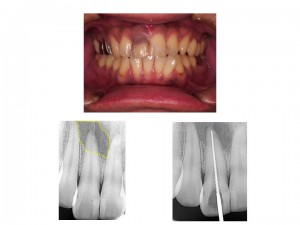

今回は、オフィスホワイトニングとホームホワイトニングの症例をご紹介します。